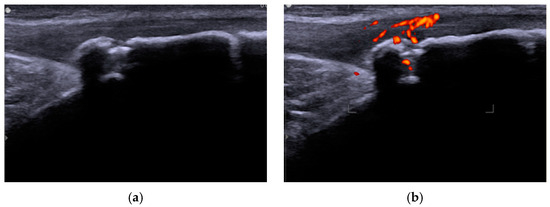

- Draghi, F.; Danesino, G.M.; Coscia, D.; Precerutti, M.; Pagani, C. Overload syndromes of the knee in adolescents: Sonographic findings. J. Ultrasound 2008, 11, 151–157. [Google Scholar] [CrossRef]

- Maruszczak, K.; Kochman, M.; Madej, T.; Gawda, P. Ultrasound Imaging in Diagnosis and Management of Lower Limb Injuries: A Comprehensive Review. Med. Sci. Monit. 2024, 30, e945413. [Google Scholar] [CrossRef] [PubMed]